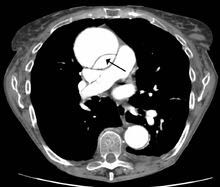

2、增强CT:常用手段。安全、简单、准确,有诊断和术前评估价值。

主动脉夹层发病时就像一个被吹大的气球。当血液从裂口进入主动脉壁,把管壁中间的那层膜撕开、分裂、扩展,大量血液涌进去,又形成一个新的血管腔。当循环血液渗入主动脉夹层之内,只能流入不能正常流出,就会像吹气球一样,越"吹"越大,最终导致主动脉破裂,病人会在瞬间死亡。大多数的患者在病发前会感觉胸痛异常,烦躁不安、大汗淋漓、有濒死感,甚至因疼痛而昏厥。不过也有一部分患者病发时毫无预兆,一发病两三分钟内猝死,无法实施抢救。